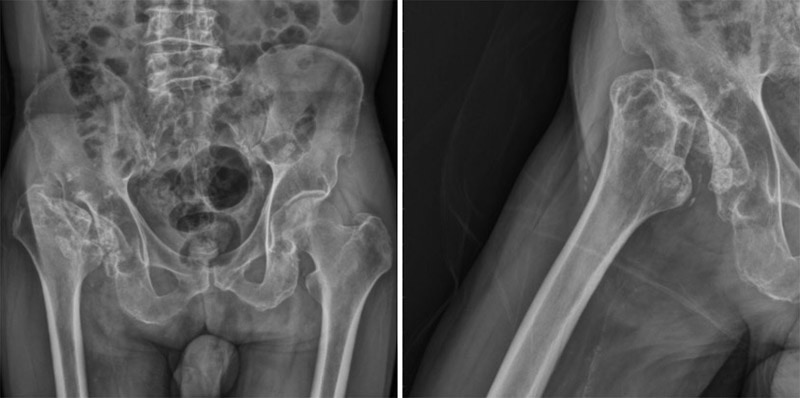

人工髖關節置換手術案例 陳奕霖醫師 永和耕莘醫院骨科醫師 永和骨科推薦